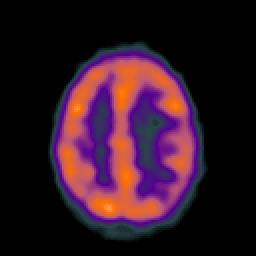

Metastatic bronchogenic carcinoma: Perfusion SPECT -- Slice #15

[Home][Help][Clinical] Slice 15